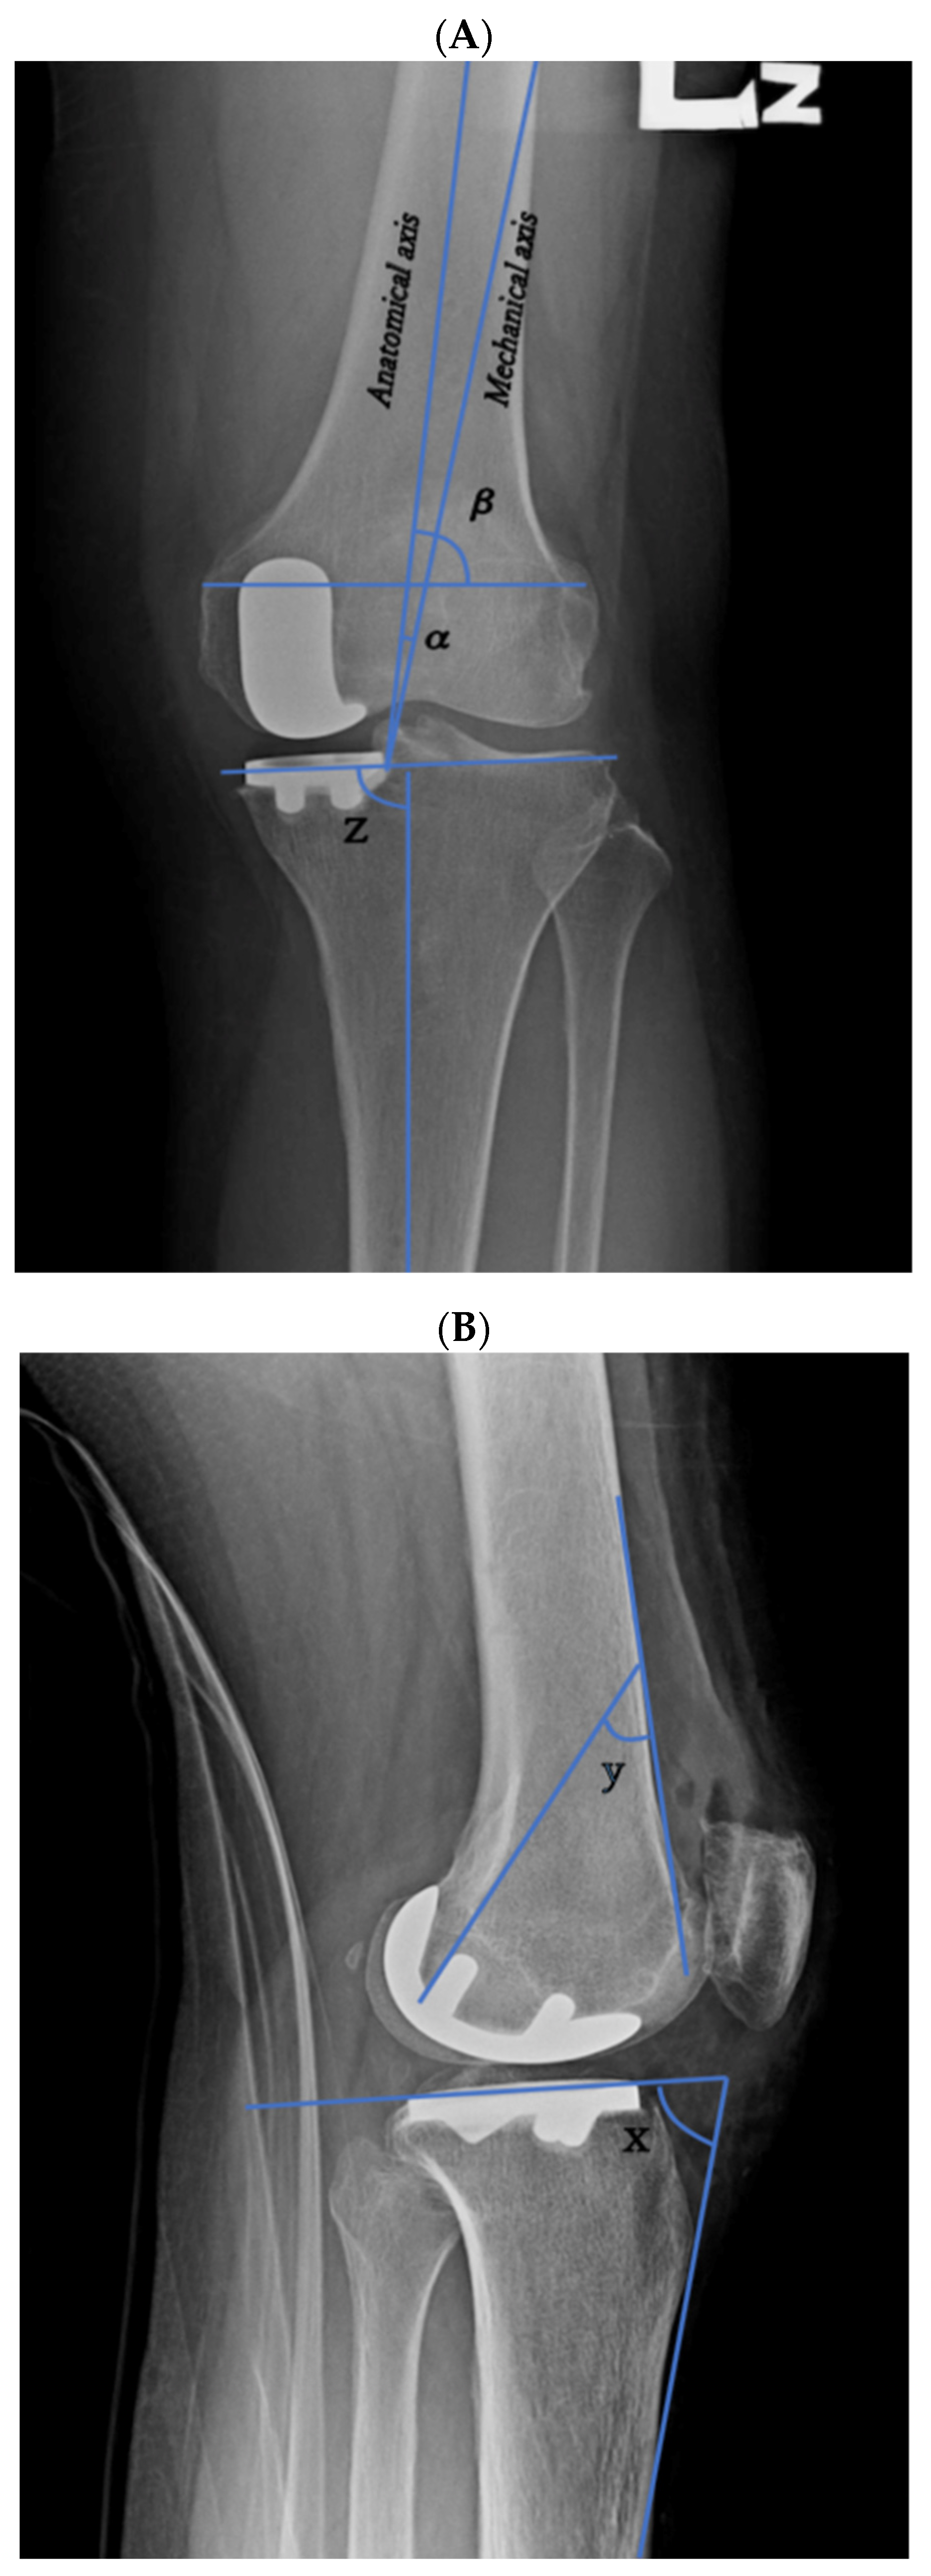

All the patients underwent preoperative and postoperative radiograph to assess bone alignment and component positioning. The bone alignment parameters were the anatomical axis angle, femoral condyle angle, femoral implant angle, tibial axis angle, and tibial slope, which were used in this study’s analysis (Figure 2A,B). These anatomical measurements were calculated using a two-dimensional knee radiograph measurement. The anatomical axis was defined as the angle between the mechanical and anatomical femoral axis on the anteroposterior (AP) knee radiograph. The anatomical femoral axis is a line drawn proximally to distally in the intramedullary canal of the femur, whereas the mechanical femoral axis is a line drawn from the center of the femoral head to the center of the knee joint [5,10,11]. The femoral condyle angle was defined as the lateral angle between the anatomical femoral axis and a line tangential to both the distal femoral condyles on the AP knee radiograph. The femoral implant angle was defined as the angle between the second hook of the posterior femoral component and the surface line of the femoral bone on the lateral knee radiograph. The tibial axis angle was defined as the medial angle between the tibial shaft axis and a line tangential to both the tibial condyles on the AP knee radiograph. The tibial slope was defined as the angle between the tibial implant and the surface line of the tibia bone on the lateral knee radiograph, which was then subtracted from 90°.

Figure 2. Radiograph parameter measurements of bone alignment and component positioning. (A) Anteroposterior view of the left knee indicating the measurement of anatomical axis angle α, femoral condyle angle β, and tibial axis angle z. (B) Lateral radiograph of the left knee indicating the measurement of femoral component angle y and tibial slope (90°—x).